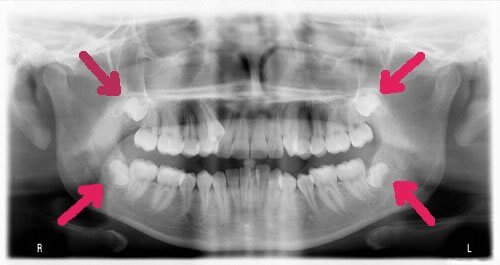

wisdom teeth removal markham, tooth extraction markham

Wisdom tooth extractions are the most common extraction procedure we perform. Most surgeons recommend that young adults have their wisdom teeth removed between the ages of 15 and 22, before the roots have completely developed. Most wisdom teeth are removed because they are impacted, and causing gum disease and decay not only on the wisdom teeth but also on the neighbouring molars. Cyst formation is not common, but can occur in some severe cases causing bone loss in the lower jaw. Another reason to extract the wisdom teeth is to provide the rest of the teeth with a little more space and less crowding. After a comprehensive examination by our doctors, we’ll inform you of the recommended treatment plan and we’ll thoroughly discuss all the details with you. It is recommended that you follow our doctors’ pre- and post-procedure instructions to guarantee the best results and a successful healing process.